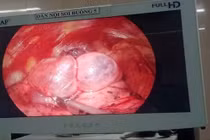

Làm chủ phẫu thuật cắt kén khí phổi ngay tại Ninh Bình

Kén khí phổi là bệnh hiếm gặp, có thể gây ra những biến chứng nghiêm trọng nhưng có thể điều trị hiệu quả nếu phát hiện sớm.

Phẫu thuật nội soi lồng ngực cắt kén khí phổi là kỹ thuật chuyên sâu, thường được triển khai tại các bệnh viện tuyến Trung ương. Việc Trung tâm Ung bướu - Bệnh viện Đa khoa tỉnh Ninh Bình làm chủ và thực hiện độc lập kỹ thuật này đã mở ra cơ hội điều trị hiệu quả ngay tại địa phương cho người dân.

Mệt mỏi, khó thở không ngờ phổi phải nhiều kén khí